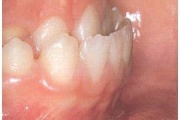

Lutipudelikaariese kahjustused

Lutipudelikaaries